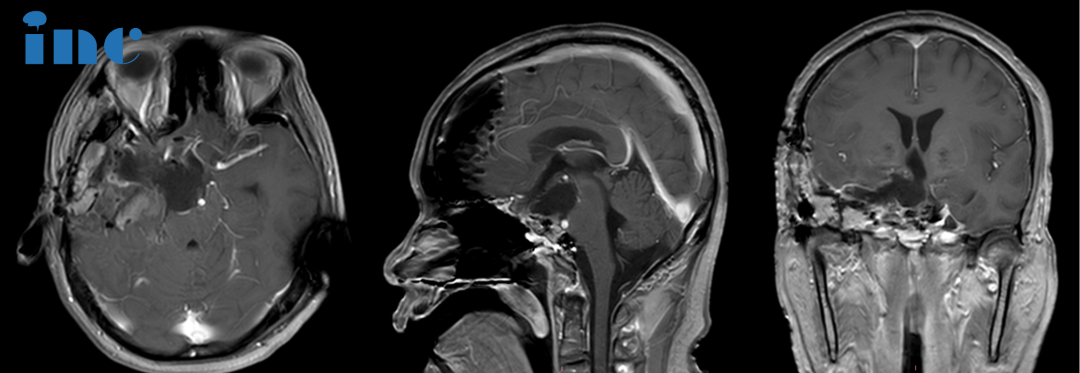

术前MRI:肿瘤体大,广泛累及颅底结构,侵蚀斜坡、鞍内鞍上、海绵窦区,包裹右侧颈内动脉。肿瘤向上推挤视神经、视交叉,到达三脑室底部;向后上方推挤脑干和基底动脉,部分肿瘤边缘与脑干分界欠清。